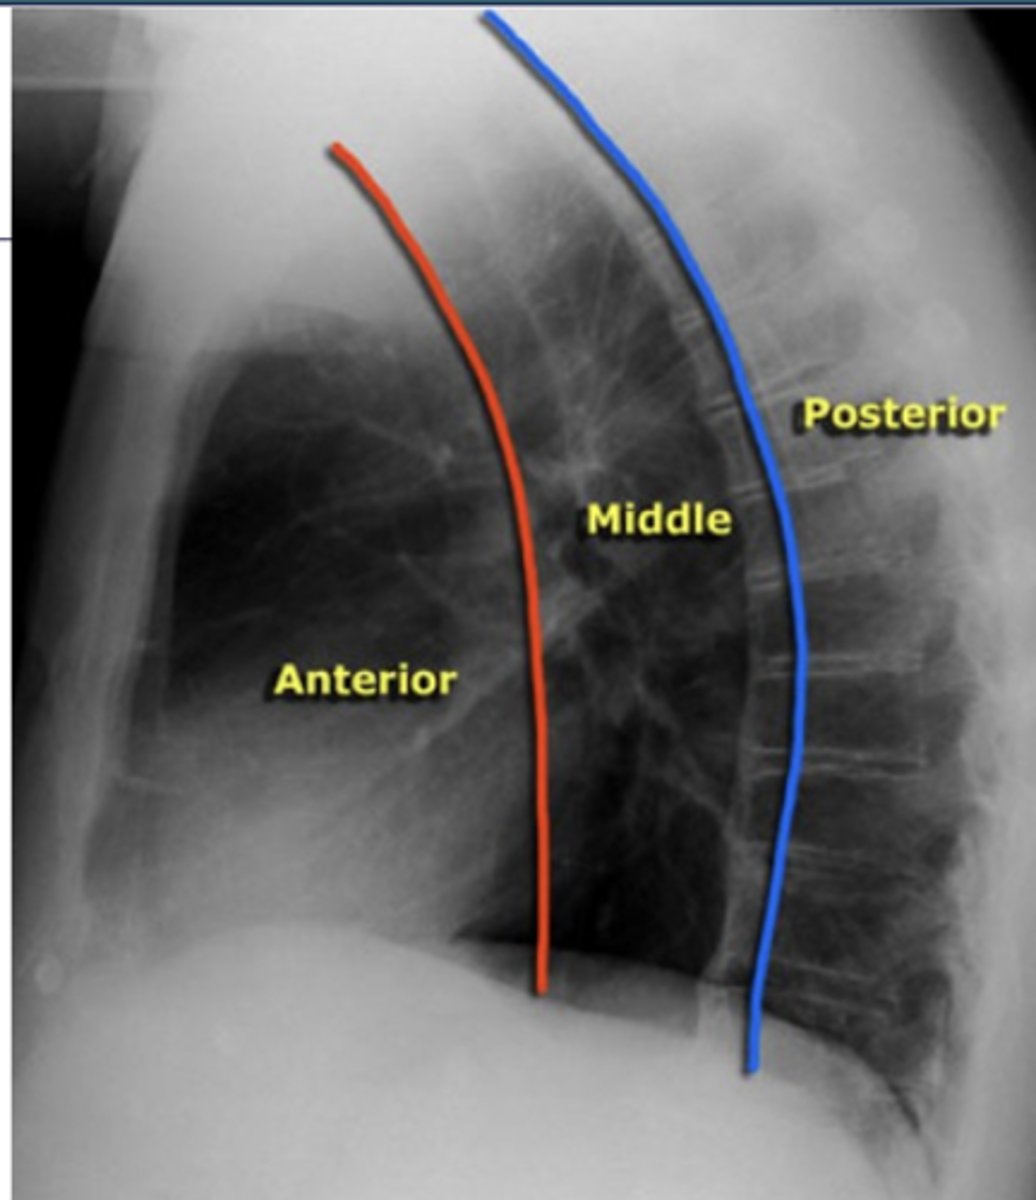

ascending aorta, aortic knob, heart, lymph nodes, thyroid, and thymus

What structures are located in the anterior mediastinal compartment?

esophagus, trachea, lymph nodes, and aortic arch

What structures are located in the middle mediastinal compartment?

descending aorta, lymph nodes, spinal nerves, and vertebral bodies.

What structures are located in the posterior mediastinal compartment?